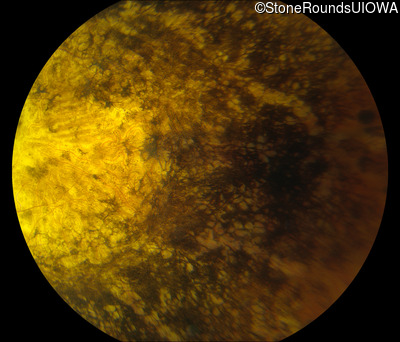

Fundus Photography - Right - Light Perception sc

Exemplar

Fundus Photography - Left - Light Perception sc

Fundus Montage - Right - Light Perception sc

Fundus Montage - Left - Light Perception sc